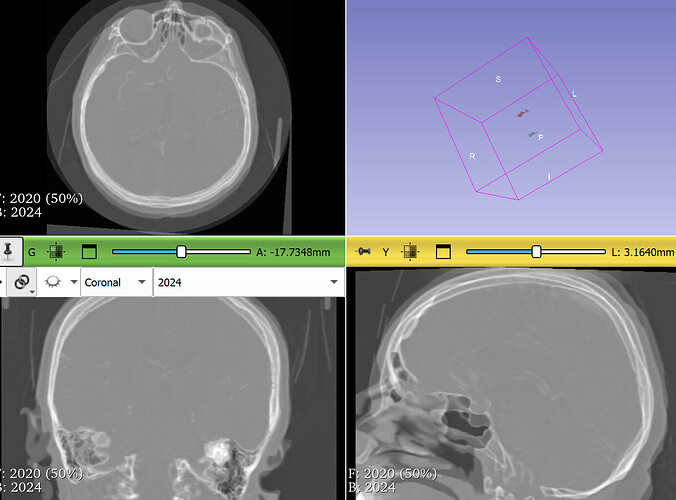

It is not a problem, I can share another patient. Basically, I pass another patients, tried to change generic, generic rigid (all), 3D CT monomodal head and neck. Every option work with different accurancy.

I’m wondering if it wouldn’t be a good idea to review my approach.

Thanks

result:

link for another CT scan: